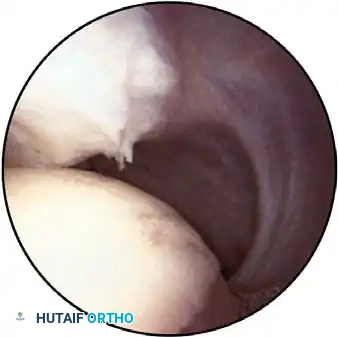

Early identification of micro-instability is paramount. Subtle instability often precipitates superior labral anterior and posterior (SLAP) lesions and secondary rotator cuff impingement. By identifying these lesions early, treatment can be directed at the root biomechanical cause rather than merely the secondary symptoms.

In the overhead throwing athlete, the shoulder is repeatedly placed in extreme abduction, hyperextension, and external rotation (the late cocking phase). This position forces the greater tuberosity and the undersurface of the rotator cuff to impinge against the posterosuperior glenoid rim and labrum. This internal impingement results in fraying of the cuff undersurface and the superior labrum. Repetitive microtrauma leads to anteroinferior ligamentous laxity and a "peel-back" of the posterosuperior capsular complex.

Appropriate surgical intervention relies on a thorough arthroscopic evaluation to decode these complex pathological findings. Diagnostic arthroscopy is also highly indicated for: